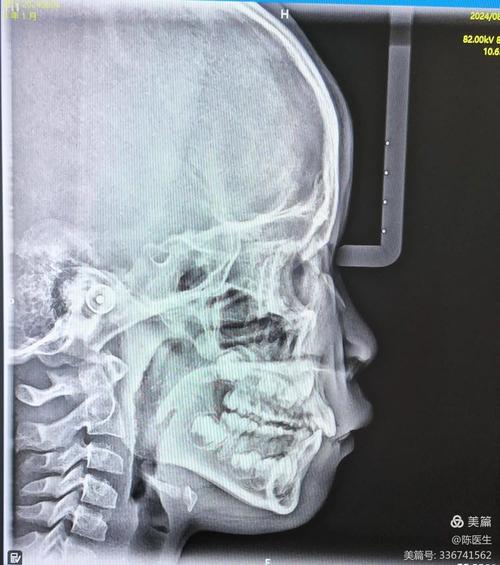

头颅侧位片(Cephalometric Radiograph)

- 成像原理: 患者头部固定于头颅定位仪上,在特定体位(通常为正中矢状面)拍摄的一张X线片,包含颅骨、颌骨、牙齿、软组织轮廓的影像。

- 核心应用:

- 骨骼分析:

- 颌骨大小与位置: 测量上下颌骨相对于颅底(如S-N平面)的前后、垂直向位置关系(如ANB角, SNA角, SNB角)。

- 颌骨形态: 评估上下颌骨的长度、高度、旋转情况如下颌平面角、Y轴角等。

- 矢状向关系: 判断安氏分类(I, II, III类错颌),分析骨性不调的原因(上颌前突/后缩,下颌前突/后缩)。

- 垂直向关系: 评估面部垂直高度(前面高、后面高、下面高),判断开颌、深覆颌、长面型、短面型等问题。

- 牙齿分析:

- 牙齿位置: 测量牙齿相对于颌骨基骨的位置(如U1-SN, L1-MP角)。

- 牙轴倾斜: 评估上下前牙的唇舌向倾斜度。

- 拥挤度/间隙分析: 结合牙冠宽度测量,评估牙量骨量是否协调。

- 软组织分析:

- 面部轮廓: 评估鼻唇角、软组织颏前点、上唇突度、下唇突度、颏部形态等。

- 美学评估: 为制定治疗目标(如微笑线、露龈笑等)提供参考。

- 生长预测: 对于生长发育期患者,通过系列头颅侧位片评估生长方向(水平向/垂直向)、生长潜力、生长量,预测未来面型变化。

- 治疗计划制定: 是制定正畸治疗目标(拔牙/非拔牙、支抗设计、颌骨移动方案等)的核心依据。

- 疗效评估: 治疗前后对比,量化评估牙齿、颌骨、软组织的改变。

- 优点: 提供标准化的二维测量数据,是正畸诊断和计划制定的金标准之一,能进行纵向生长研究。

- 局限性: 二维影像,无法准确反映颌骨的三维形态和结构,对颏部、髁突等结构显示不佳,存在影像重叠和放大失真,软组织轮廓是二维投影。